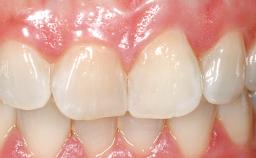

A 30-year-old female patient had lost tooth 21 and was referred to our clinic for consultation and treatment. Due to advanced apical infection, tooth 21 had been extracted two months earlier at another clinic and an acrylic-resin tooth had been bonded to the adjacent teeth. The patient desired implant treatment to avoid any damage to the adjacent natural teeth. While the patient had no history of any systemic disorder, she was a heavy smoker and exhibited medium to advanced periodontitis in the entire jaw. After the initial treatment to achieve a pocket probing depth of less than 4 mm and no bleeding on probing, a decrease in the height of the papillae mesial and distal to the extraction site and overall gingival recession were observed.

Abutment Type CAD/CAM

Prosthesis Type FDP

SAC Level Complex

Defining Characteristics One missing tooth to be replaced by an implant-borne crown

Esthetic Risk High